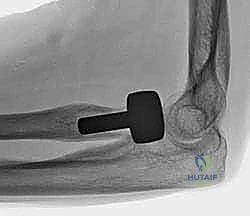

5. تركيب الغرسة المعيارية (Modular Implantation)

يتم إدخال "الجذع" (Stem) داخل القناة العظمية للكعبرة، ثم يتم تركيب "الرأس" (Head) المعدني فوقه. الميزة هنا أن النظام "معياري"، أي يمكن تركيب رأس بحجم معين على جذع بحجم مختلف، ليتناسب تماماً مع تشريح المريض.